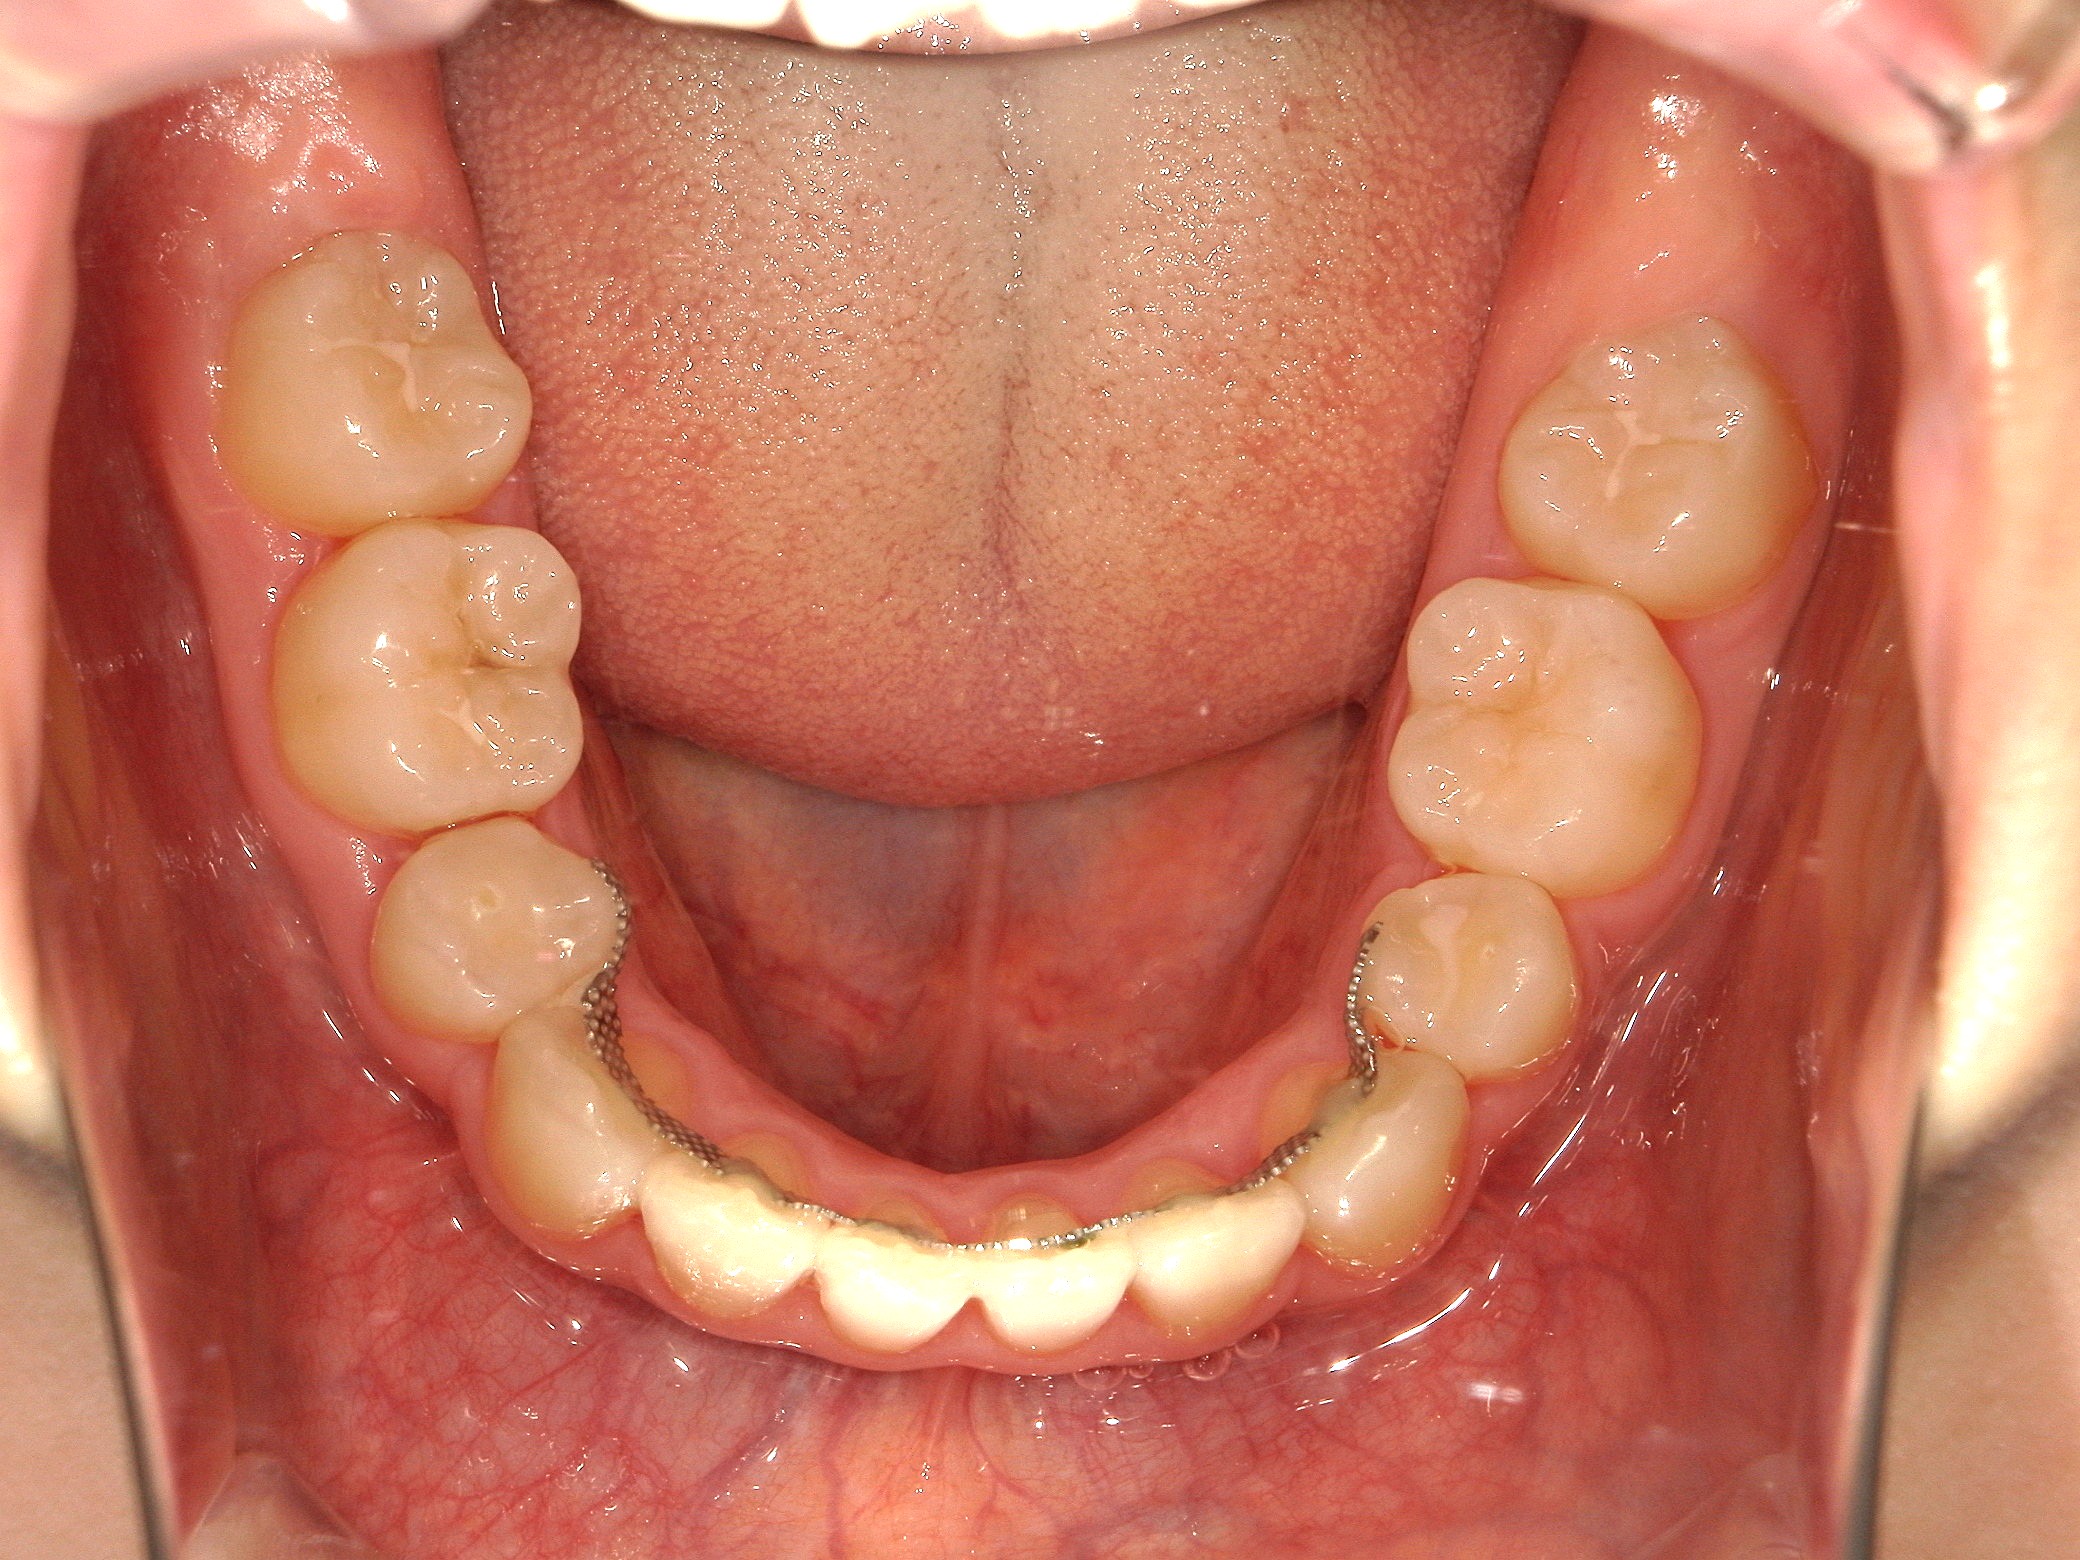

口内下

治療前

治療後